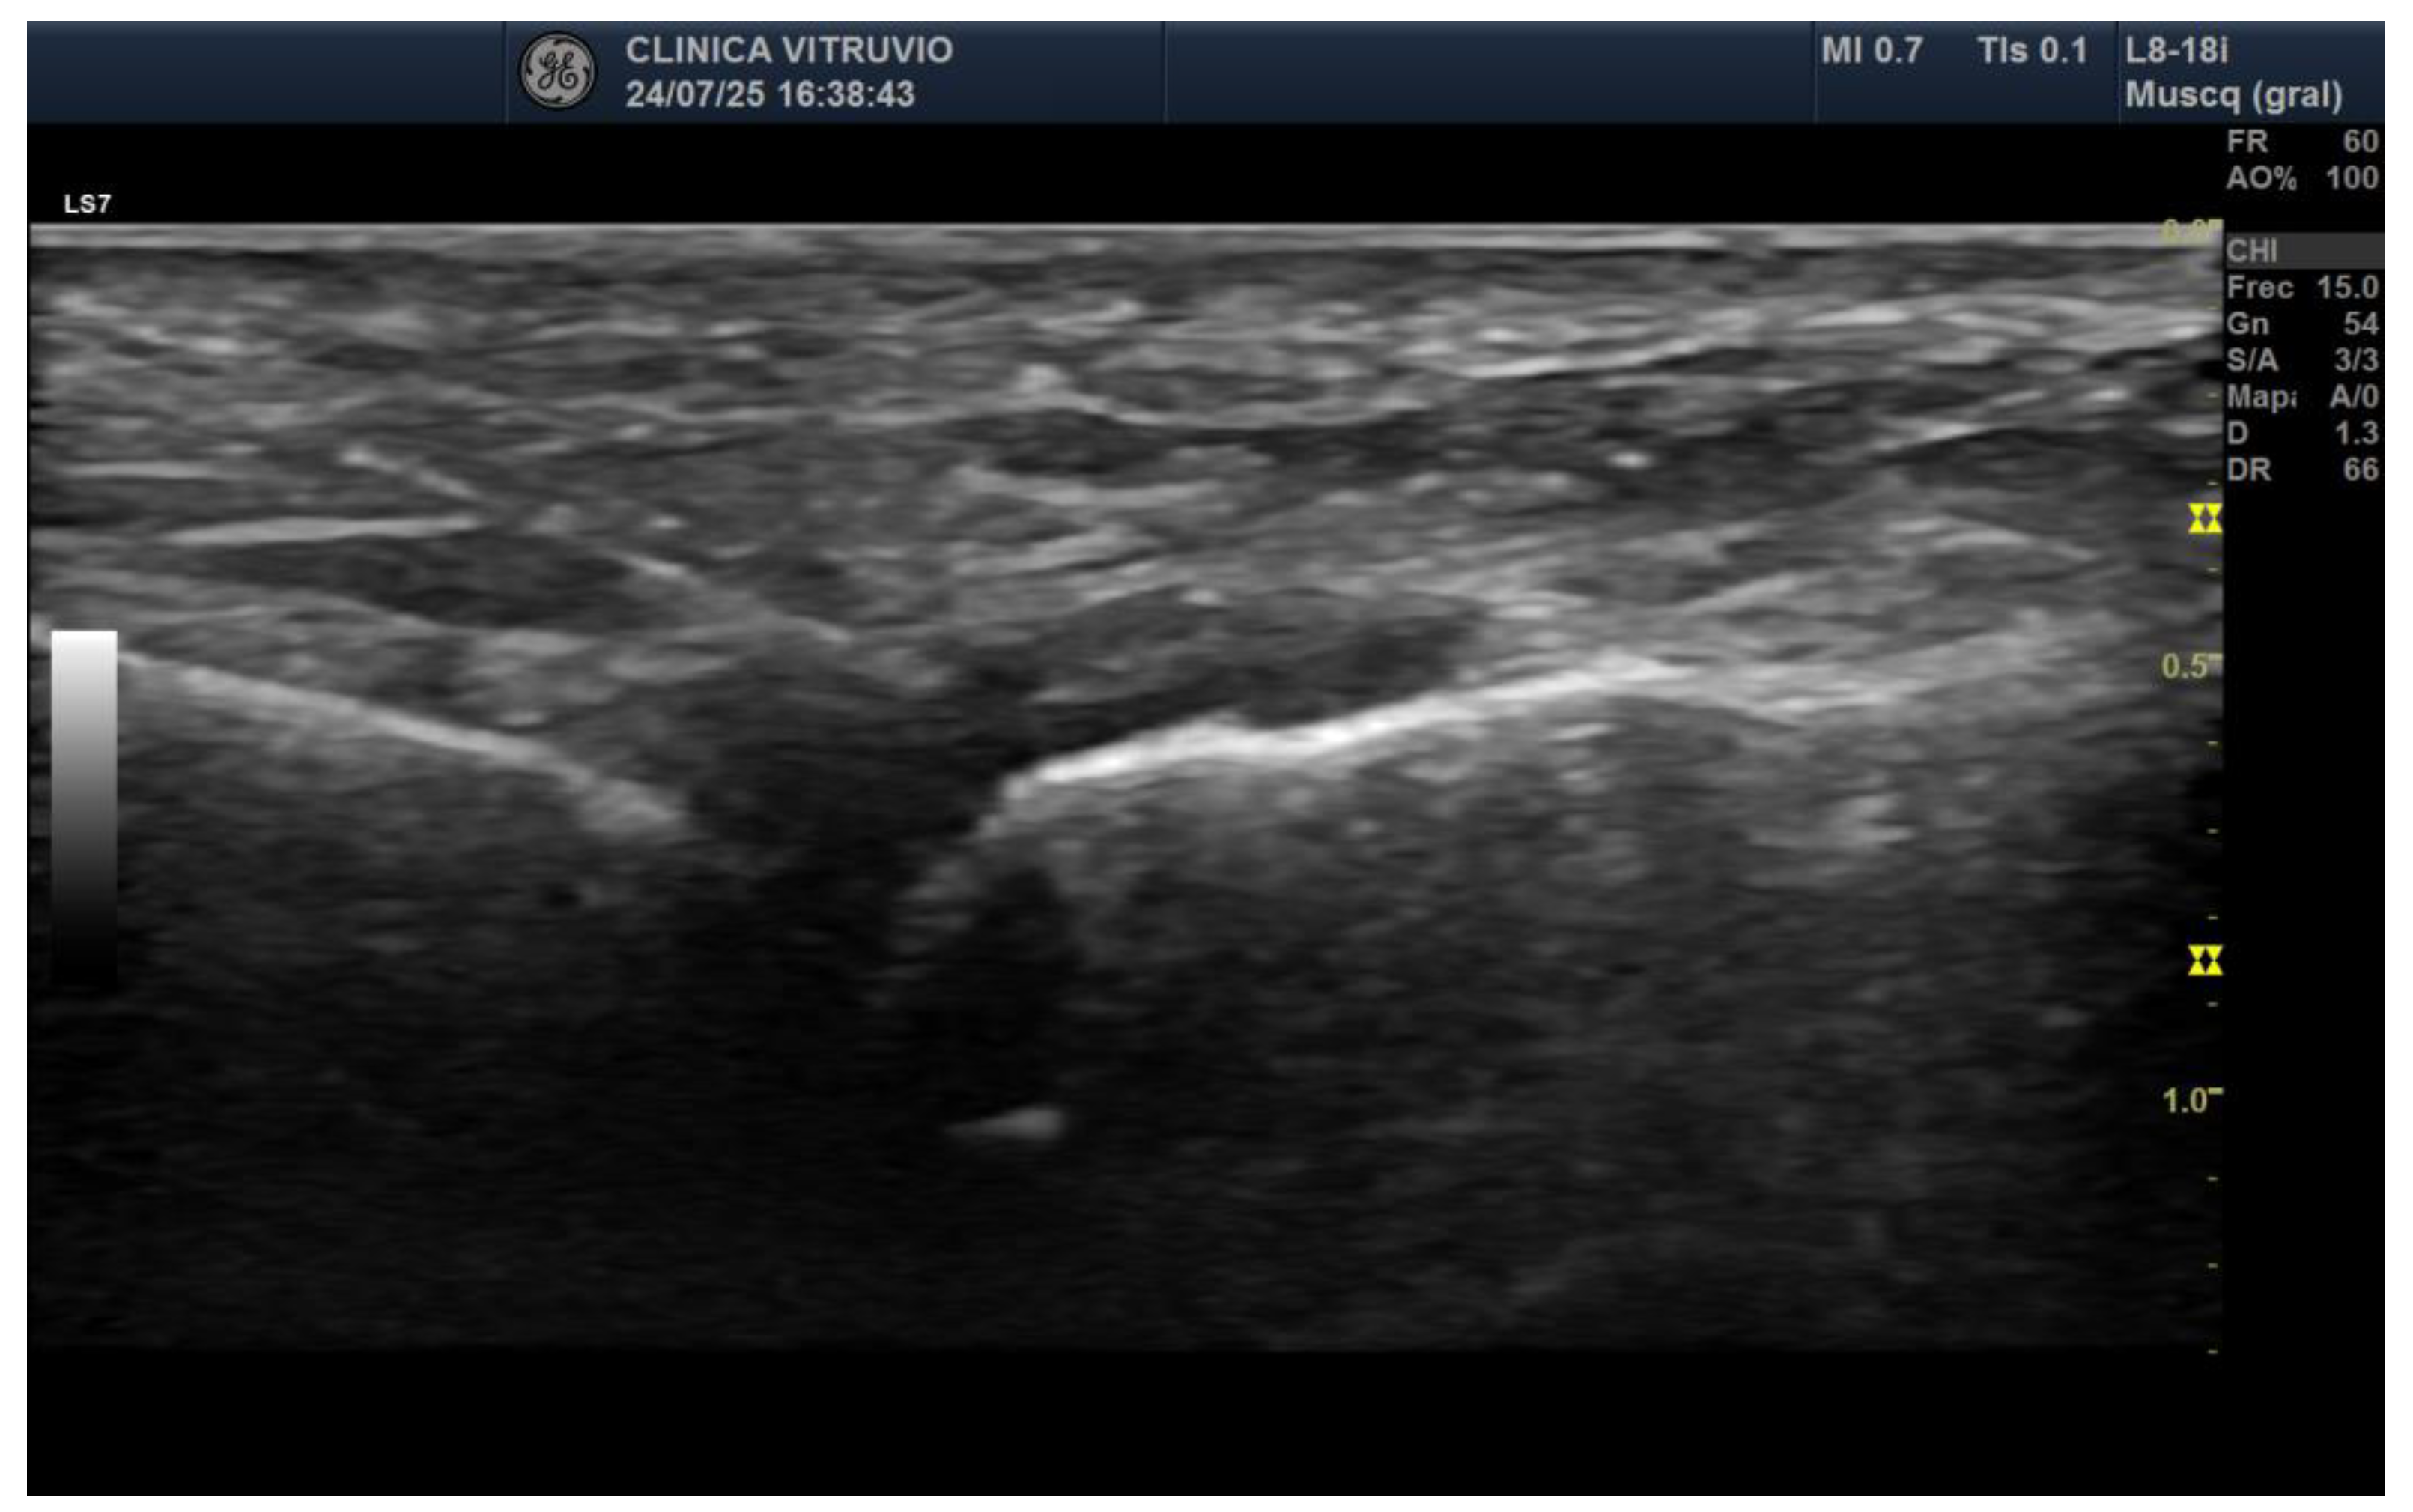

In all intra-articular injections (n = 12), iodinated contrast dispersion remained confined within the articular capsule (Figure 2). Radiographic images revealed a contained, symmetrical pattern with sharply defined margins and an ovoid or triangular morphology, depending on the projection plane. The distribution of contrast was homogeneous in all joints, with no evidence of extravasation into the collateral ligaments, dorsal capsule, or pericapsular regions. These findings support the hypothesis that the MTP joint functions as a closed, sealed cavity, offering a significant anatomical advantage for performing selective and reproducible diagnostic blocks.

Figure 2. Dorsoplantar radiograph of the right forefoot following intra-articular injection of radiopaque contrast. A volume of 0.5 cc was injected into the second metatarsophalangeal joint, 0.4 cc into the third, and 0.3 cc into the fourth. Complete filling of the joint cavities is observed without contrast extravasation, confirming the sealed capsular nature of each articulation.